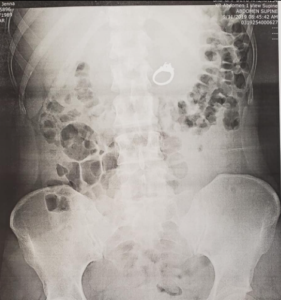

Otišli smo na hitnu gdje sam im jedva objasnila što se dogodilo jer sam se istovremeno smijala i plakala. Liječnik je naručio rentgen i izgledao je prilično šokirano kad se vratio s ostalim liječnicima, pokazao mi je da, da je moj prsten stvarno u mom trbuhu! Nazvali su gastroenterologa i zaključili da je najbolje NE prepustiti stvari prirodi. (Hvala Bogu).